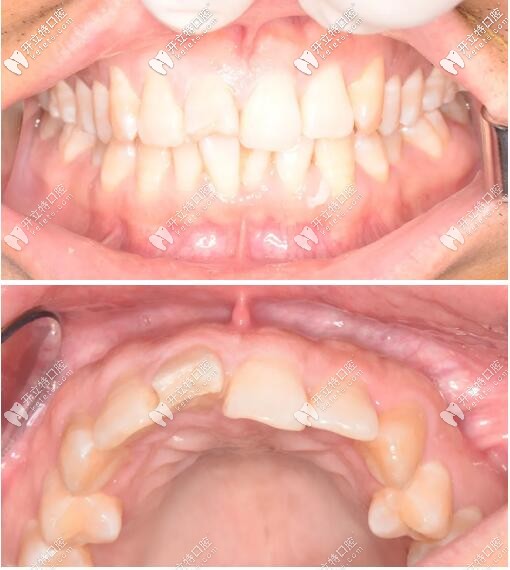

術(shù)后三個月復查見近遠中齦乳頭高度維持良好,唇側(cè)較豐滿。

門牙外傷即刻種植牙三個月后

對比臨時冠戴入即刻、戴入一個月、戴入兩個月,可見牙齦乳頭逐漸冠向生長,由圓頓變尖銳,充滿鄰間隙。

過渡義齒修復齦乳頭變化

三周后戴入全瓷修復體,紅白美學效果理想;

門牙瑞士iti鈦親水4.1mm*10mmBL種植體修復案例

戴牙一年后復診,口內(nèi)正面觀及側(cè)面像。

門牙磕傷瑞士iti種牙修復1年后